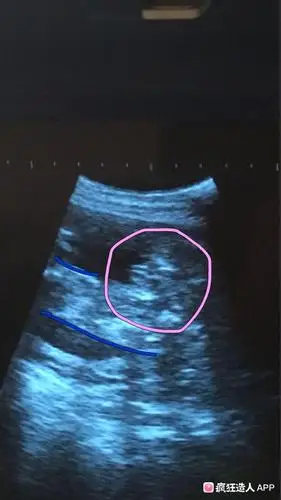

[试管婴儿]b 超图 大神帮看看是传说中的三条线么?

这个是三条线吗是不是女宝

b超有两点基本是男孩(二)【看b超图】1,b超图上有"三条线"的标记,大